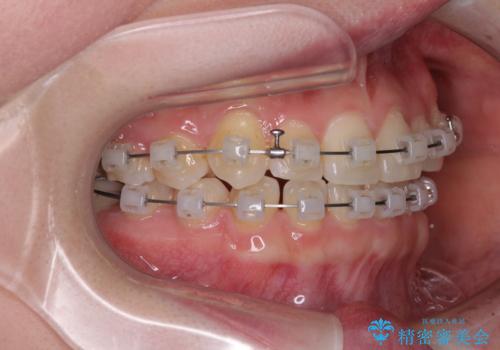

- クリアブラケット

- 1年3ヶ月

口腔内の状況を確認したところ、左右ともに下顎第二大臼歯が欠損しており、咬み合うべき上顎の第二大臼歯が著しく挺出していました。

挺出した大臼歯を元の位置に戻すことは現実的に難しいため抜歯することとし、補助装置とワイヤー装置により上顎歯列全体を後方に移動することとしました。

順調に後方移動することができ、わずか1年強で治療を終えることができました。